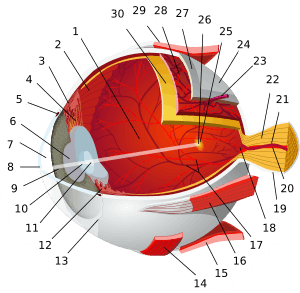

Light from a single point of a distant object and light from a single point of a near object being brought to a focus by changing the curvature of the lens. | |

The structures of the eye labeled

Another view of the eye and the structures of the eye labeled